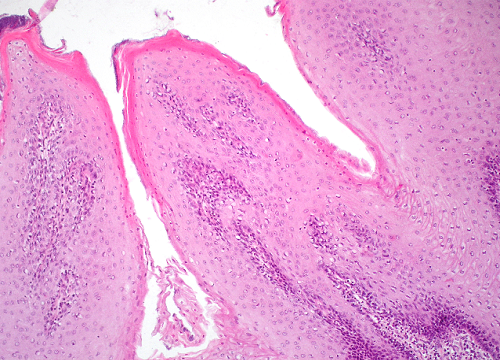

Question 4

Question

Label this image

Image:

923e7534-e40a-4fab-a487-f781ceacfa5a (image/jpeg)

Answer

Adult tooth